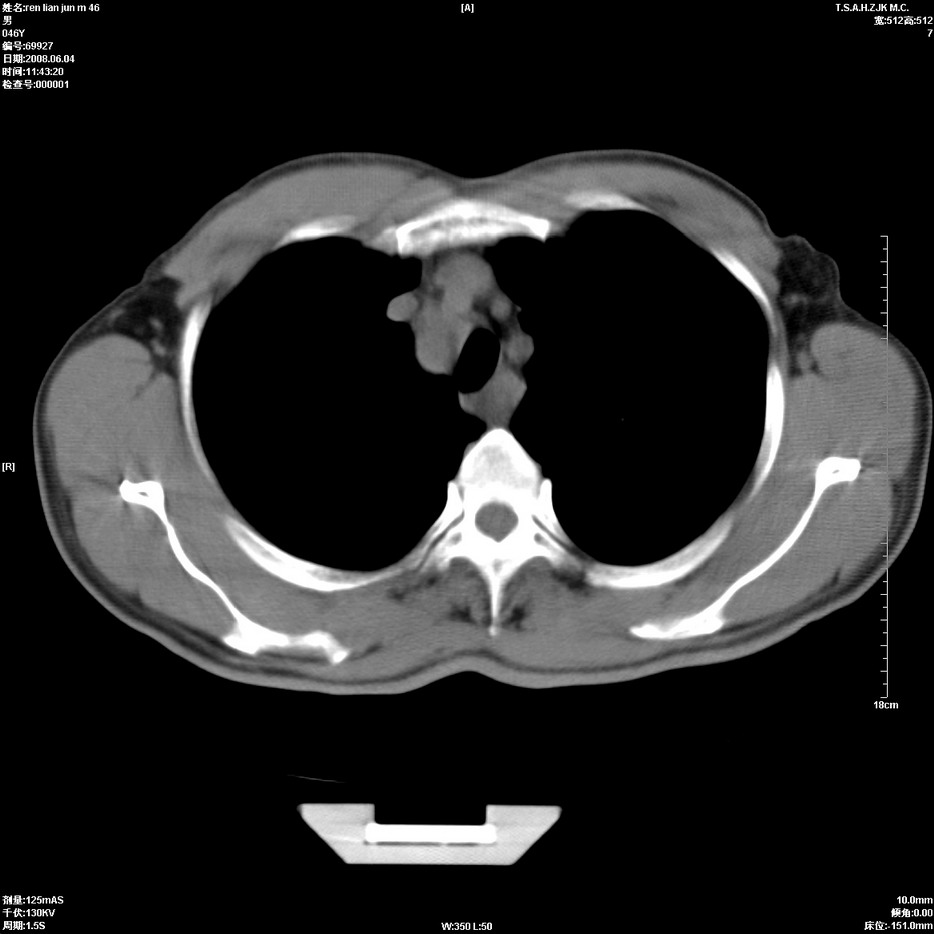

以下是引用qiu999在2008-6-5 17:14:00的发言:[br]考虑右肺中心型肺癌.颅内应做增强检查.

以下是引用形影不离在2008-6-5 19:18:00的发言:[br]右肺中心型肺癌并纵隔及左侧腋窝淋巴结转移,颅内应做增强检查。

以下是引用杀毒软件在2008-6-5 18:33:00的发言:[br]支持考虑右肺中心型肺癌,颅内病变是不是转移,不好说